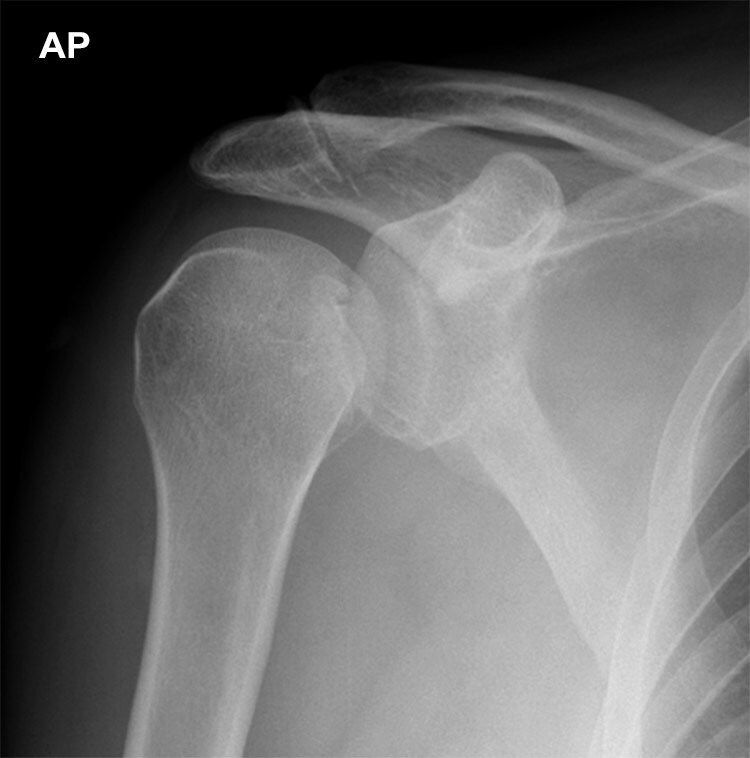

X-RAY QUIZ: Which finding is present on this image?

Start Quiz bit.ly/36i1txn